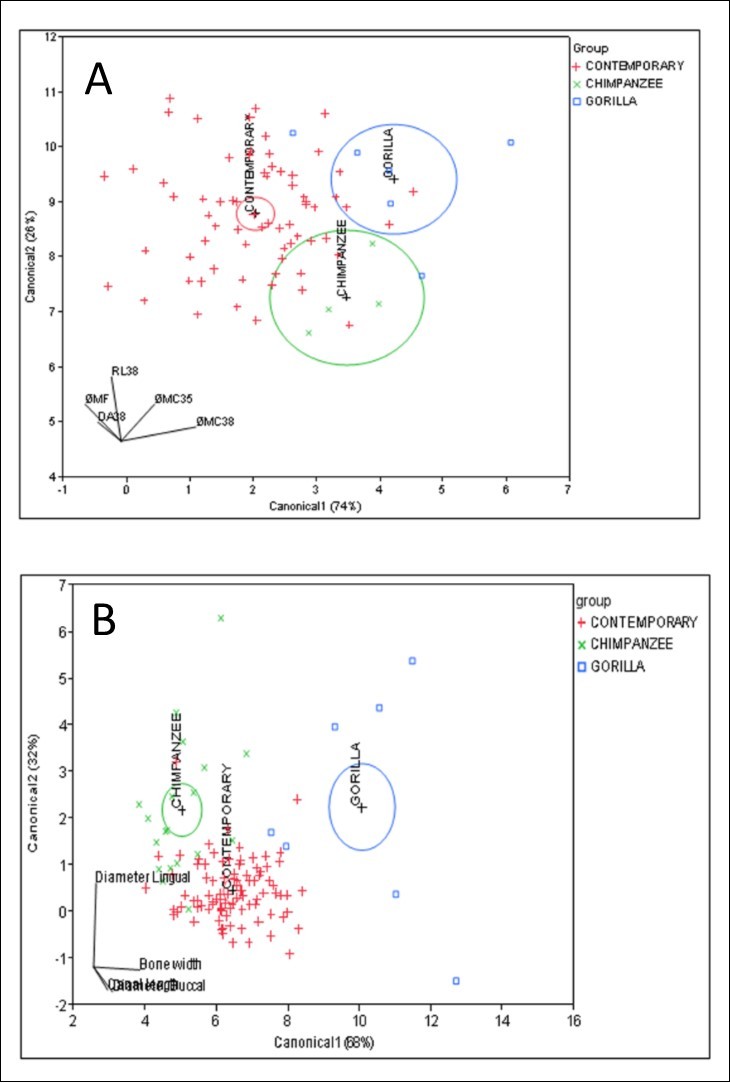

Different distributions were observed in the lingual canal, related to its vertical and horizontal position. Regarding to the horizontal position, this canal was mostly found at the midline in Human, whereas it was frequently found in the midline and left position in Gorilla and Chimpanzee. Vertically, it was more frequently observed above the superior genial tubercles in humans, in contrast to a more middle position in Chimpanzee and Gorilla groups. A higher number of extra lingual canals were also observed in Chimpanzee group. Multivariate analysis showed variable redundancies, patterning in data sample group differentiation between Gorilla, Chimpanzee and contemporary Human mandibles, without overlapping in their distributions (Figure 5).

Figure 5.Linear discriminant analyses from the canonical plots show interspecific results of neurovascular canal features between Gorilla (*), Chimpanzee (Í) and contemporary Human mandibles (+), with distinctive, non-overlapping distributions in (A) and (B). RL 38: root length of #38 tooth; DA38: distance canal to root apex of #38 tooth; φMC38: the diameter of mandibular canal at molar #38; φMC35: the diameter of mandibular canal at premolar #35; φMF: the diameter of mandible mental foramen.